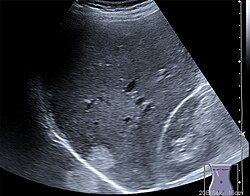

Die Sonde sendet kurze, gerichtete Schallwellenimpulse aus, die an Gewebe-Grenzschichten und in inhomogenen Geweben unterschiedlich stark reflektiert und gestreut werden, was als Echogenität bezeichnet wird. Aus der Laufzeit der reflektierten Signale kann die Tiefe der reflektierenden Struktur ermittelt werden. Die Stärke der Reflexion wird vom Ultraschallgerät als Grauwert auf einem Monitor dargestellt. Strukturen geringer Echogenität werden dunkel bzw. schwarz, Strukturen hoher Echogenität werden hell oder weiß dargestellt. Gering echogen sind vor allem Flüssigkeiten wie Harnblaseninhalt und Blut. Eine hohe Echogenität besitzen Knochen, Gase und sonstige stark schallreflektierende Material-Grenzflächen. Die Echogenität innerhalb eines Organs oder eines Krankheitsherdes wird als Binnenecho bezeichnet.

Von den Monitorbildern werden zur Dokumentation Ausdrucke, sogenannte Sonogramme, oder gelegentlich Videoaufnahmen gemacht. Schwangeren wird häufig auch ein Bild ihres ungeborenen Kindes überlassen.

B-Mode (B für englisch brightness modulation) ist eine andere Darstellung der Information des Amplituden-Modus, bei der die Echointensität in eine Helligkeit umgesetzt wird. Durch mechanisches Bewegen der Sonde überstreicht der Messstrahl eine Fläche in einer Ebene ungefähr senkrecht zur Körperoberfläche. Der Grauwert eines Bildpunktes auf dem Bildschirm ist ein Maß für die Amplitude eines Echos an dieser Stelle.

2D-Echtzeitmodus (2D-realtime)

Im 2D-Echtzeitmodus, der derzeit häufigsten Anwendung des Ultraschalls, wird ein zweidimensionales Schnittbild des untersuchten Gewebes durch automatische Verschwenkung des Messstrahls und Synchronisierung der B-mode- Darstellung in Echtzeit erzeugt. Das Schnittbild wird dabei aus einzelnen Linien zusammengesetzt, wobei für jede Linie ein Strahl ausgesendet und empfangen werden muss. Die Form des erzeugten Bildes hängt dabei vom eingesetzten Sondentyp ab. Der 2D-Echtzeitmodus kann mit anderen Verfahren wie dem M-Mode oder der Doppler-Sonografie gekoppelt werden. Je nach Eindringtiefe und Sondentyp können nur einige wenige oder bis zu über hundert zweidimensionale Bilder pro Sekunde dargestellt werden.